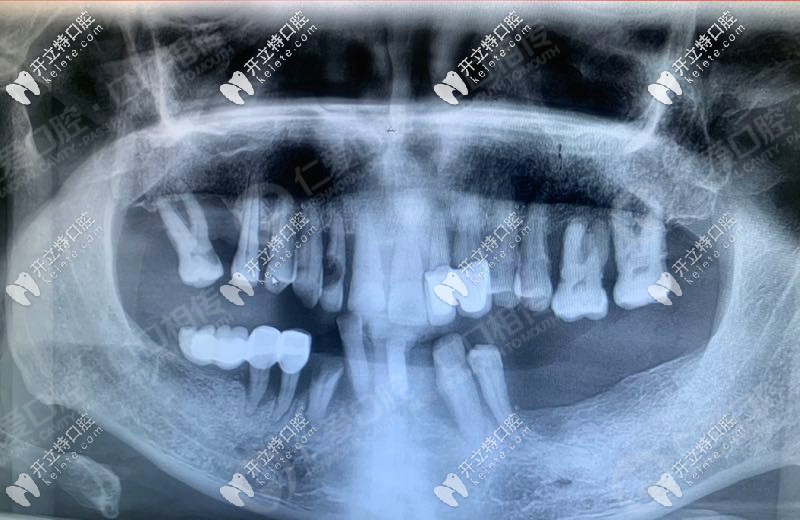

3d導(dǎo)板+all-on-6半口即刻負(fù)重,讓武漢老人當(dāng)天種植牙當(dāng)天用

即刻負(fù)重人工種植牙發(fā)布時(shí)間: 2024-11-13

多顆缺失、半口牙缺失老人如何種牙?大波圖,了解下3d導(dǎo)板即刻負(fù)重半口種植牙技術(shù),當(dāng)天種牙,當(dāng)天用。